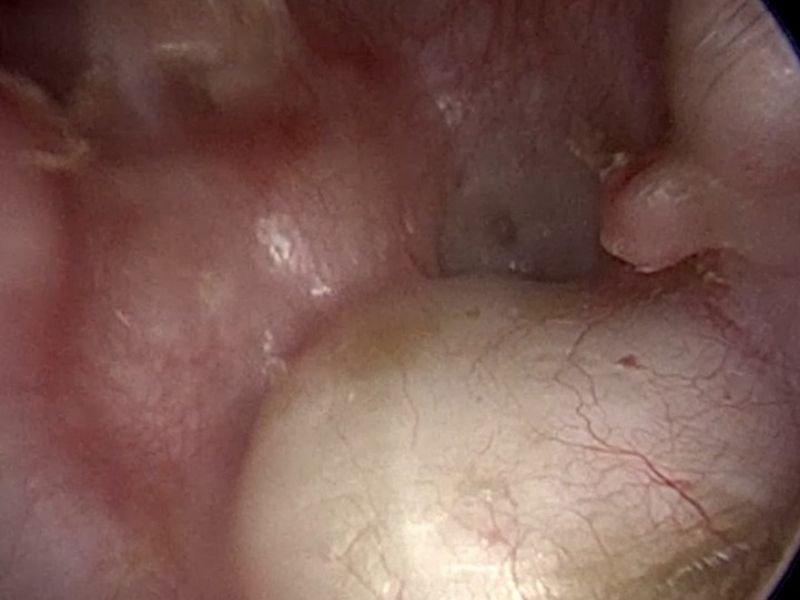

O Dr. André Maranhão é especialista em procedimentos cirúrgicos otológicos, com um foco específico em tratamentos para surdez, otosclerose, infecções crônicas e outras condições relacionadas ao ouvido. Entre as cirurgias realizadas, destacam-se a timpanoplastia, para a reconstrução do tímpano danificado, e a estapedotomia, um procedimento para tratar a otosclerose, uma doença que causa rigidez dos ossículos do ouvido médio, afetando a audição.

As cirurgias endoscópicas também são uma opção inovadora e minimamente invasiva para o tratamento de doenças do ouvido, proporcionando menos dor, menos tempo de recuperação e melhores resultados estéticos. O uso da endoscopia permite que o Dr. André Maranhão realize procedimentos delicados com uma precisão incomparável.